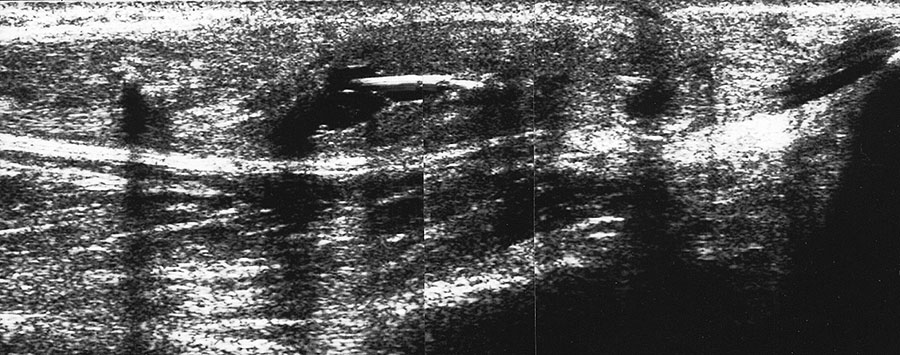

Durch Druck auf die ventrale Tibia läßt sich der Talusvorschub testen

Abbildung 20

Lagerung: Rückenlage, OSG in Plantarflexion, bei chronischer Instabilität auch Bauchlage.

Schnittebene: LS über Lig. talofibulare anterius und Lig. fibulocalcaneare.

Referenzstrukturen: Fibula und Talushals.

Befunde: Zunächst werden wie oben ausgeführt Lig. fibulotalare anterius und Lig. fibulocalcaneare im direkten Bandschnitt dargestellt. Dann erfolgt im Seitenvergleich die Stabilitätstestung unter Sicht auf den Monitor. Durch Druck von oben auf den Unterschenkel wird ein Vorschub des Fußes gegenüber der Tibia erzeugt, so dass, allerdings nicht in jedem Fall einer Banddurchtrennung, ein Vorschub des Talus gegenüber der Fibula (immer im Seitvergleich) am Monitor gemessen werden kann 3.